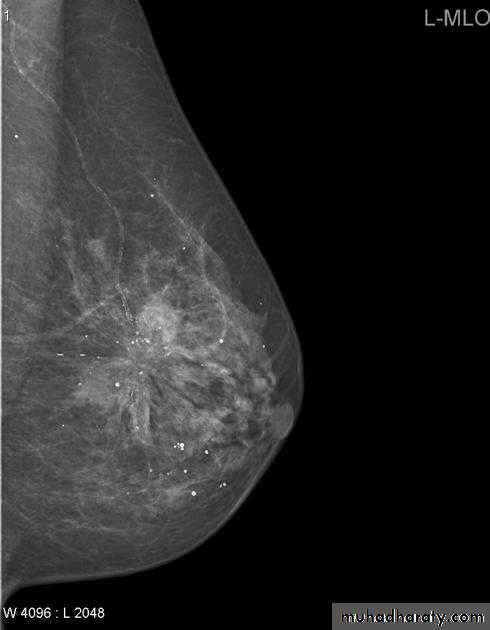

The mediolateral oblique (MLO) view is one of standard mammographic views. It is the most important projection as it allows to depict most breast tissue.

Breast density & who can U detect a mass lesion

Your mammogram report must take in consideration & assessment the breast density. Breast density is based on how fibrous and glandular tissue tissues are distributed in your breast, vs. how much of your breast is made up fatty tissue.

Dense breasts are not abnormal, but they are linked to a higher risk of breast cancer. We know that dense breast tissue can make it harder to find cancers on a mammogram. Still experts do not agree what other tests, if any, should be done in addition to mammograms in women with dense breasts who aren’t in a high-risk group (based on gene mutations, breast cancer in the family, or other factors